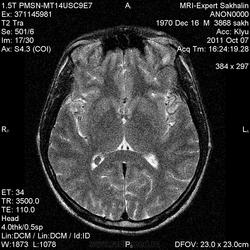

МРТ головного мозга.Туберозный склероз?

Уважаемые коллеги, сегодня обратился молодой человек , самостоятельно приехал из района.Я обратила внимание на наличие  подкожных образований на лице по типу фибром .После проведения исследования поговорила с ним-кожные проявления с детства, обследовался,якобы подозревали нейрофиброматоз.МРТ прошел  впервые сегодня.

А что в желудочках-это потоковые артефакты?

Если в задних рогах, то это сосудистые сплетения.

Я тоже что ничего не вижу, в задних рогах похоже на сосудистые сплетения, согласна с Nela. Так к слову: У меня недавно была молодая девочка, похожие изменения в желудочках, ради эксперимента и ознакомления сделали программу swi. Так в одном желудочке действительно было сосудистое сплетение, а во второй заподозрили мальформацию. Сейчас проходит полное обследование, если подтвердится обязательно выложу.

Гамартомы в стенках желудочков выглядят очень специфически, не спутаете.

Непривычно для глаз потому, что сплтения не совсем нормальные. Некоторые трактуют такие изменения как последствия тромбоза.